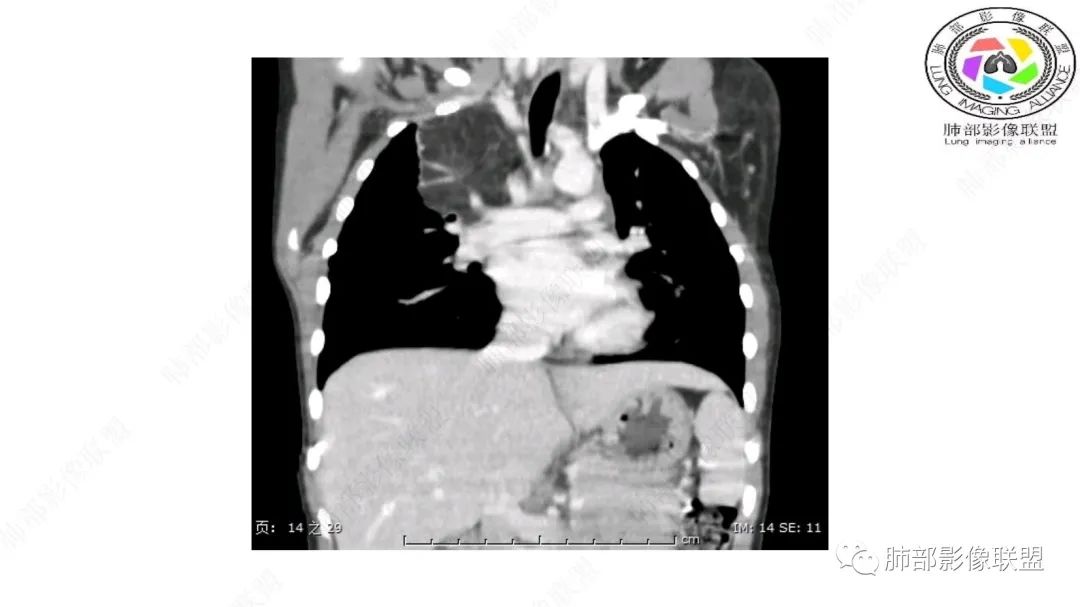

右上纵隔混杂密度肿块,边缘光整,与纵隔分界清,其内多发脂肪密度,增强无明显强化,其内血管穿行,考虑纵隔脂肪母细胞瘤,鉴别畸胎瘤,脂肪肉瘤。

右纵隔团状,密度不均,脂肪密度为主,内可见腺体样组织,类似乳腺,病灶边缘有分叶,与胸腺关系密切,增强后血管穿行。考虑胸腺脂肪瘤(不典型垂乳征),鉴别畸胎瘤。

定位:肺内?尖段气管未见明显显示,腔静脉受压向右推移?病灶内可见前段动脉穿行,脂肪密度为主。

肿块起源于右上气管分叉处?强化动脉血管最后汇入右肺动脉上干。

右侧纵隔奇静脉水平起源?压迫上肺,包绕动脉?

跨肺门,包绕肺血管分支,邻近肺组织受压肺不张。

可以看到造影剂进入的丛状结构

密度不均,非纯脂肪成分。斑片状密度略高区域有轻度填充式强化。

病灶属于交界区,主体位于肺内,占位效应明显,前方突入胸壁,胸腺受压变形,胸膜显示欠清楚;病灶包绕上叶肺动脉;似乎有体动脉供血。符合肺内的点:包绕上叶肺动脉分支;符合纵隔的点:前方似乎突入胸壁,与胸腺关系比较密切,但是与上腔静脉的关系提示病灶不支持纵隔来源,前纵隔的常规会将上腔静脉受压后移、外移,这是不符合的。

2.肺动脉穿行也许是肺内来源最重要支持点!

脂肪母细胞瘤由成熟程度不同的脂肪组织、纤维间隔、黏液基质、小血管丛等间质成分组成,以脂肪组织与黏液样基质为主,其影像学表现取决于上述组织成分。典型的CT和MRI表现为:前后纵隔均可发生,常见于前纵隔;肿块大小不一,直径多在3cm~7cm,密度均匀,CT值呈水样或脂肪密度,脂肪组织密度或信号为主的肿块,其内密度或信号不均匀,可见粗细不一的分隔影,且有结节、片状影,后者可呈轻中度强化;结节状肿瘤包膜完整;弥漫性者包膜不明显,常呈浸润性生长;周围结构为受压和推移改变,可有少量胸腔积液,淋巴结无增大。